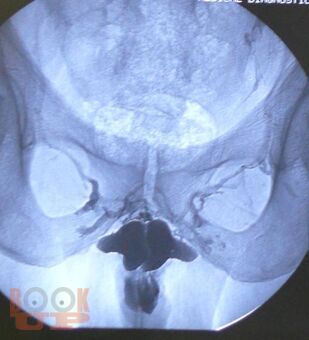

Динамическая кавернозография в диагностике патологии кавернозного бассейна полового члена

В учебном пособии представлены вопросы метода рентгеновского исследования заболеваний кавернозного бассейна полового члена, некоторые анатомо-физиологические аспекты эрекции, показания и противопоказания к проведению динамической кавернозографии, описана методика проведения динамической кавернозографии, а также представлен разработанный авторами алгоритм обследования пациентов с эректильной дисфункцией. Учебное пособие предназначено для врачей рентгенологов и урологов.